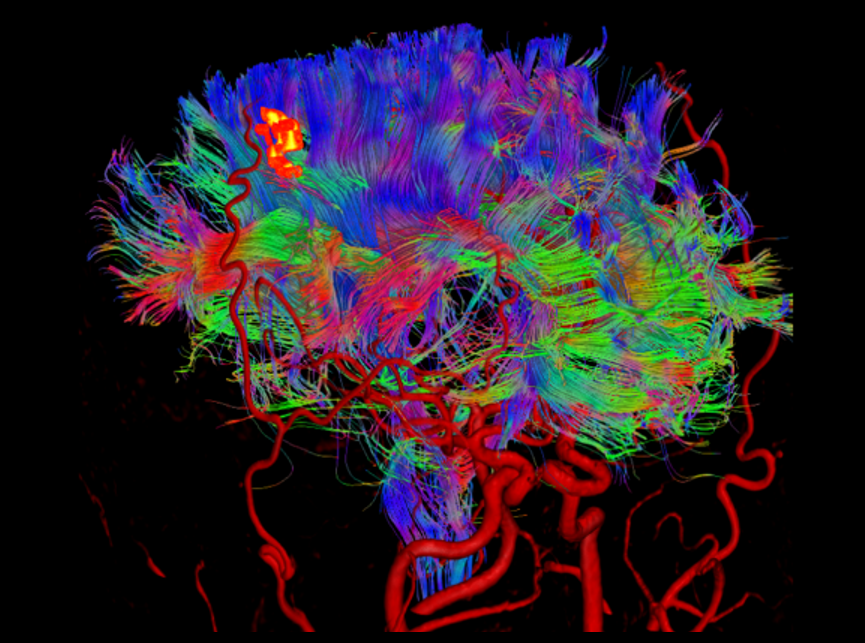

搭载uAIFI Technology技术平台,凝聚多项全球首创核心技术,全链条革新磁共振硬件、软件设计,实现系统性能、扫描智能化、成像速度与信噪比的大幅提升,同时赋予患者更舒适的检查体验,开启磁共振“类脑”时代。

在uMR 880上,我们将全身型磁共振的梯度性能推向了新的高度。更高的梯度梯度性能在弥散扫描时可以帮助用户获得更短的TE时间以提升信噪比同时得到更准确的弥散模型。